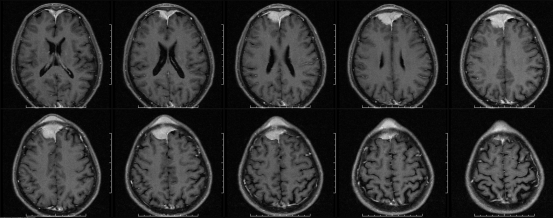

62岁的郭大爷,1年前洗头时发现额部有一杏仁大小、质地较硬的包块。2015年3月份,郭大爷自觉额头包块增大,乍眼一看竟像一个“犄角”。这可急坏了郭大爷,他便去当地多家医院就医,被诊断为“额骨软骨瘤”,治疗多次均无效果。最终向朋友打听,满怀希望来到西安凤城医院神经外科就诊。曾在西京医院从事神经外科工作10余年、临床经验丰富的王冰主任格外重视,带领神经外科医疗团队反复详细做术前检查。经磁共振(图1)显示“额部占位性病变”,考虑“矢状窦脑膜瘤”,需要尽早进行手术切除。王冰主任向郭大爷家属讲明病情、手术方式、风险及并发症后,家属表示理解并知情,积极要求手术。

图1

(术前磁共振)